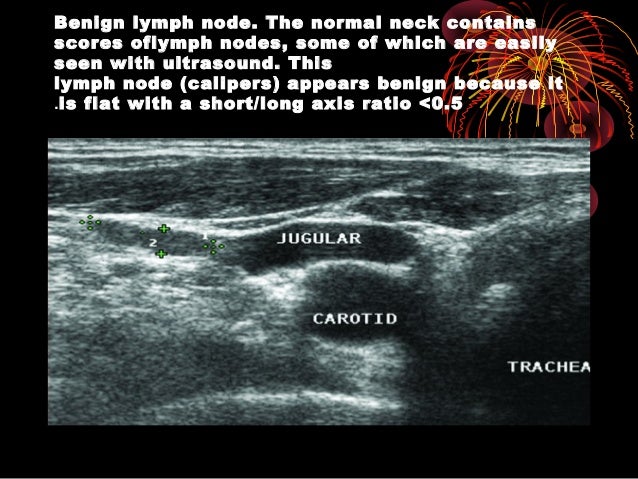

Thyroid Ultrasound

thyroid lymph nodes benign